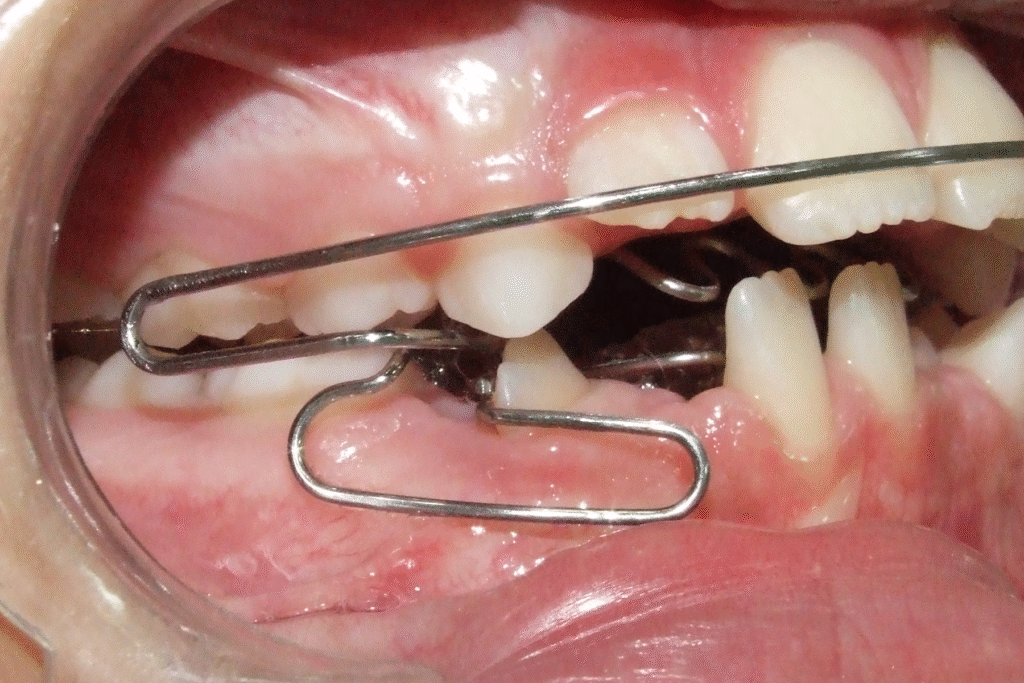

Alguns casos de oclusopatia, com alterações de desenvolvimento, distúrbios funcionais e oclusais, necessitam de tratamento imediato em idade oportuna. A Ortopedia Funcional dos Maxilares (OFM) apresenta recursos técnicos para uma intervenção com o intuito de corrigir ou melhorar as alterações presentes. Deste modo, os efeitos e sequelas decorrentes da oclusopatia tornam-se muito menores, facilitando assim o tratamento ortodôntico com aparatologia fixa. O propósito deste trabalho foi apresentar um caso clínico complexo envolvendo distoclusão com mordida aberta, alterações funcionais e irrupção ectópica do incisivo lateral inferior direito – tratado inicialmente em uma fase importante de desenvolvimento com OFM e, em seguida, em uma fase final com Ortodontia fixa.